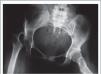

Rotación de extremidades inferioresEl procedimiento de elección para la marcha en rotación interna secundaria a una anteversión femoral aumentada, es la Osteotomía femoral proximal intertrocantérea desrotadora(10). La anteversión femoral frecuentemente se encuentra aumentada en pacientes con PC y se ha reportado que los resultados de su corrección, perduran en el tiempo con seguimiento a más de 5 años de evolución, especialmente si la cirugía es realizada después del crecimiento rápido (10,11).